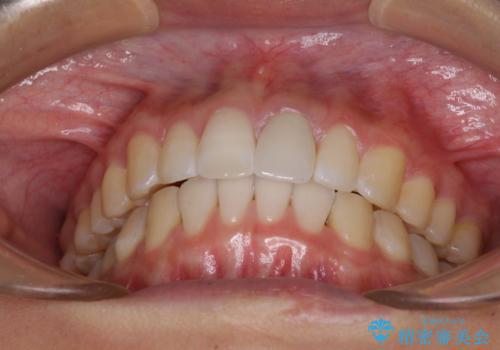

- 変色した前歯と突出した口元を気にして来院された患者様です。

口元の突出感はインビザラインにより歯列を整え、その後に、前歯をオーダーメイドタイプのオールセラミッククラウンにて補綴治療することとしました。

長時間のマウスピース装着と、患者様自身でのゴムかけに協力いただき、口元の突出感をしっかりと改善することができました。

前歯のオールセラミッククラウンもまるで本物の歯のように仕上がり、患者様には大変満足していただきました。